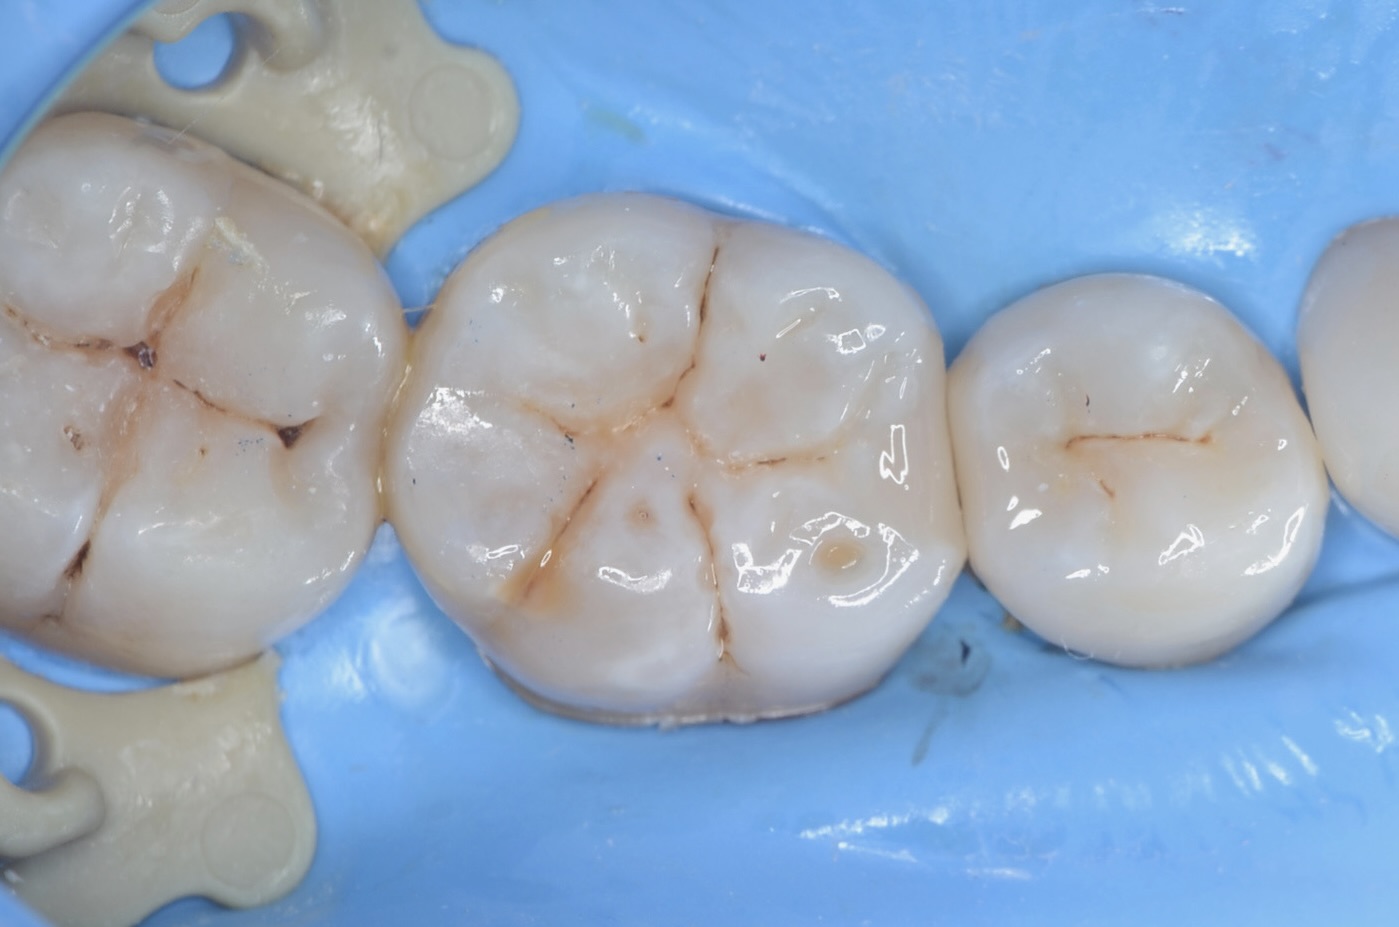

ラバーダム装着

虫歯治療においてもラバーダム装着は必須です。 唾液や血液から歯面が汚染されるのを防ぎ、乾燥状態を保つラバーダムは、接着力を向上させるためにも大切なアイテムです。 -

咬合面観

ダイレクトボンディング終了

セパレーターで歯間離開させながら光を当てながらレジンを硬化させる3Dプリンターテクニックを用いて治療しました。 -

研磨後

研磨をしっかり丁寧にすることで、レジンと歯質の段差を修正し、虫歯になりにくくします。